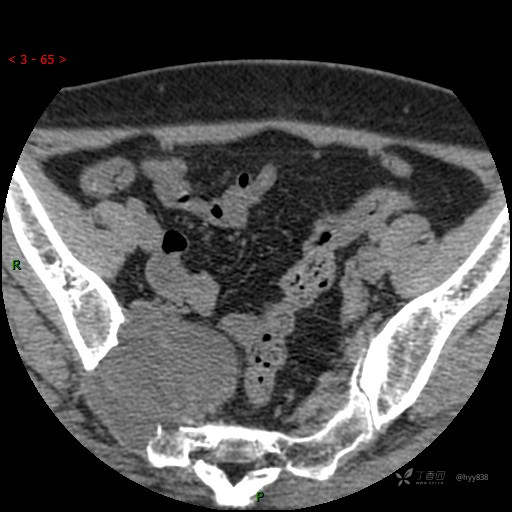

骶髂关节CT平扫